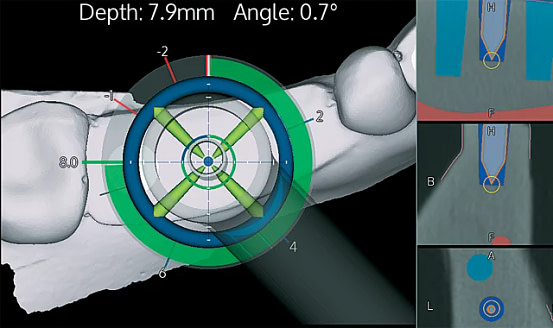

Calibration In Dynamic Navigation Surgery In Implamt

Browse our specialized Calibration In Dynamic Navigation Surgery In Implamt portfolio with numerous expertly curated photographs. optimized for both digital and print applications across multiple platforms. providing reliable visual resources for business and academic use. Each Calibration In Dynamic Navigation Surgery In Implamt image is carefully selected for superior visual impact and professional quality. Perfect for marketing materials, corporate presentations, advertising campaigns, and professional publications All Calibration In Dynamic Navigation Surgery In Implamt images are available in high resolution with professional-grade quality, optimized for both digital and print applications, and include comprehensive metadata for easy organization and usage. Our Calibration In Dynamic Navigation Surgery In Implamt collection provides reliable visual resources for business presentations and marketing materials. Whether for commercial projects or personal use, our Calibration In Dynamic Navigation Surgery In Implamt collection delivers consistent excellence. The Calibration In Dynamic Navigation Surgery In Implamt archive serves professionals, educators, and creatives across diverse industries. Regular updates keep the Calibration In Dynamic Navigation Surgery In Implamt collection current with contemporary trends and styles. Advanced search capabilities make finding the perfect Calibration In Dynamic Navigation Surgery In Implamt image effortless and efficient. Multiple resolution options ensure optimal performance across different platforms and applications.